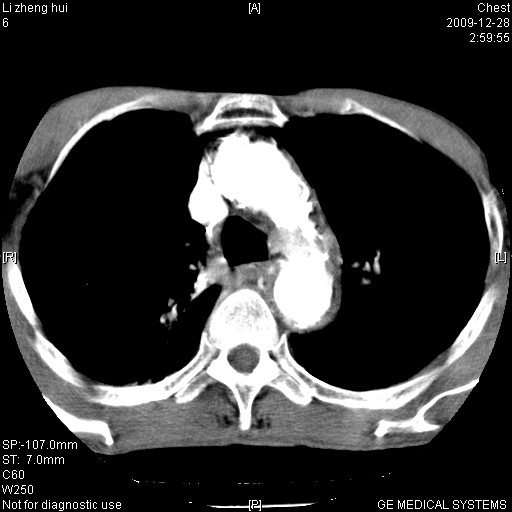

标题: CT23859:胸主动脉瘤

男  79岁 胸部痛急诊入院,晚上做的增强

考虑主动脉瘤?(增粗、钙化、壁血栓?)

1)考虑胸主动脉壁间血肿或夹层动脉瘤。2)多发性肝囊肿。

1)考虑胸主动脉附壁血栓或夹层动脉瘤。2)多发性肝囊肿。

考虑大动脉炎,附壁血栓形成。